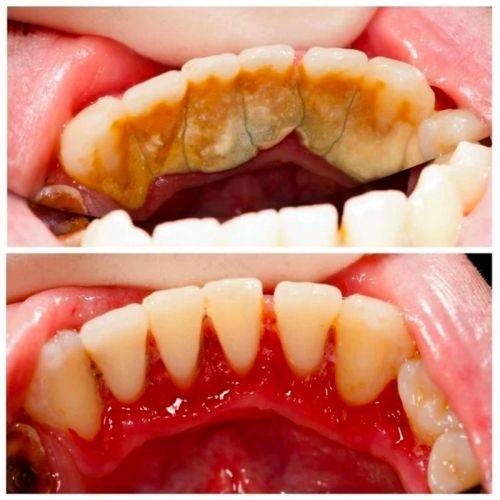

对于大部分人来说,洗牙(龈上洁治)间隔半年或一年洗一次比较好。这是因为在日常生活中,我们的牙齿表面会不断地积累牙菌斑和食物残渣。即使我们每天认真刷牙,也特别难完全清除这些物质。随着时间的推移,牙菌斑会逐渐钙化形成牙石,牙石不仅会影响牙齿的美观,还会刺激牙龈,引发牙龈炎、牙周炎等口腔疾病。

半年到一年的时间,牙齿表面积累的牙菌斑和牙石量通常会达到一个需要清理的程度。此时进行洗牙,可以有效地去除牙石和牙菌斑,预防口腔疾病的发生。而且这个频率也比较符合大多数人的生活节奏和口腔卫生状况,既不会因为洗牙过于频繁对牙齿造成不必要的损伤,也不会因为间隔时间过长而导致牙石积累过多。

要确定自己合适的洗牙频率,首先可以观察自己牙齿表面的情况。如果发现牙齿表面经常有黄色或黑色的污垢,刷牙特别难清除,或者牙龈容易出血、红肿,那么可能牙石已经积累较多,需要缩短洗牙的间隔时间。